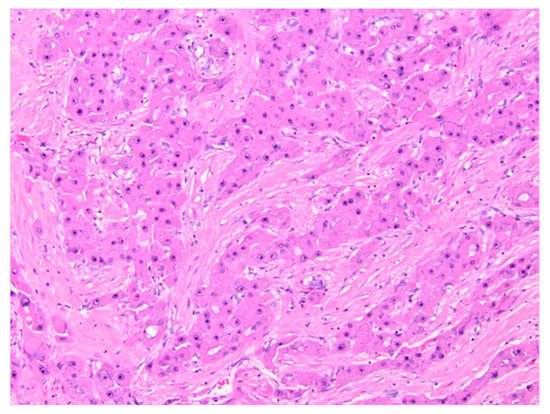

5.1.5. Histopathology and Immunohistochemistry